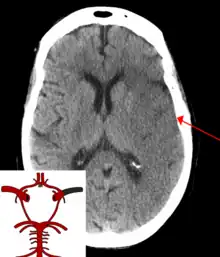

| CT scan of the brain showing a prior right-sided ischemic stroke from blockage of an artery. Changes on a CT may not be visible early on.[1] | |

The main risk factor for stroke is high blood pressure.[6] Other risk factors include tobacco smoking, obesity, high blood cholesterol, diabetes mellitus, a previous TIA, end-stage kidney disease, and atrial fibrillation.[2][6][7] An ischemic stroke is typically caused by blockage of a blood vessel, though there are also less common causes.[12][13][14] A hemorrhagic stroke is caused by either bleeding directly into the brain or into the space between the brain's membranes.[12][15] Bleeding may occur due to a ruptured brain aneurysm.[12] Diagnosis is typically based on a physical exam and supported by medical imaging such as a CT scan or MRI scan.[8] A CT scan can rule out bleeding, but may not necessarily rule out ischemia, which early on typically does not show up on a CT scan.[9] Other tests such as an electrocardiogram (ECG) and blood tests are done to determine risk factors and rule out other possible causes.[8] Low blood sugar may cause similar symptoms.[8]

Stroke is diagnosed through several techniques: a neurological examination (such as the NIHSS), CT scans (most often without contrast enhancements) or MRI scans, Doppler ultrasound, and arteriography. The diagnosis of stroke itself is clinical, with assistance from the imaging techniques. Imaging techniques also assist in determining the subtypes and cause of stroke. There is yet no commonly used blood test for the stroke diagnosis itself, though blood tests may be of help in finding out the likely cause of stroke.[63]

For diagnosing ischemic (blockage) stroke in the emergency setting:[64]

- CT scans (without contrast enhancements)

- sensitivity= 16% (less than 10% within first 3 hours of symptom onset)

- specificity= 96%

CT scans may not detect an ischemic stroke, especially if it is small, of recent onset, or in the brainstem or cerebellum areas. A CT scan is more to rule out certain stroke mimics and detect bleeding.[9]